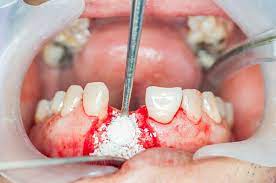

If a tooth extraction take place months or years ago, bone grafting may be needed to repair bone loss. The white you are seeing is bone. What kind of material do we use? If your child's tooth is loose and ready to fall out, you might have questions about how you can help them. Tooth extraction does not need to scare baby teeth and other teeth that could be loose due to issues of gum disease are normally easiest to pull out.

I know the graft will take many months to heal. Losing baby teeth is a rite of passage for children. Correcting bony and tissue defect with synthetic bone graft and soft tissue graft in aesthetic zone. The tooth wasn't stong enogh to pull out in one peice, so she had to lossen the bone around. This means that the site will then be ready to receive a dental implant. How long does it take to recover from a tooth extraction? When i go get a extraction done would i need to get a bone graft done at the same time or can i get it done later? However, because the patient must heal fully from the bone graft before dental implants can be placed, this procedure does extend the treatment timeline. Anyway i'm just wondering how long it takes to be all the way out and if we're in for more pain? It takes about 6 weeks for the jaw bone and gum tissue to repair itself following wisdom teeth extractions. , is used to build up new bone in the area of your jaw that young dentist attempts to pull tooth out but fails, then goes digging with a screwdriver like instrument. Often times a bone graft is placed in the tooth socket to hold the bone open and make it easier to place how does the oral surgeon determine if i am candidate for implants? Bone graft surgery for jaw bone loss socket grafts, ridge splitting, basic augmentation find answers how to fix treat repair replace options.